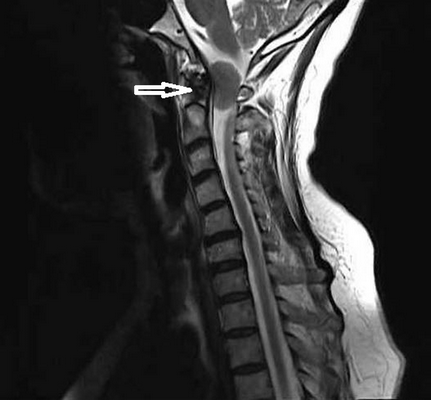

Опухоль краниовертебральной области (обозначена стрелкой)

Платибазия